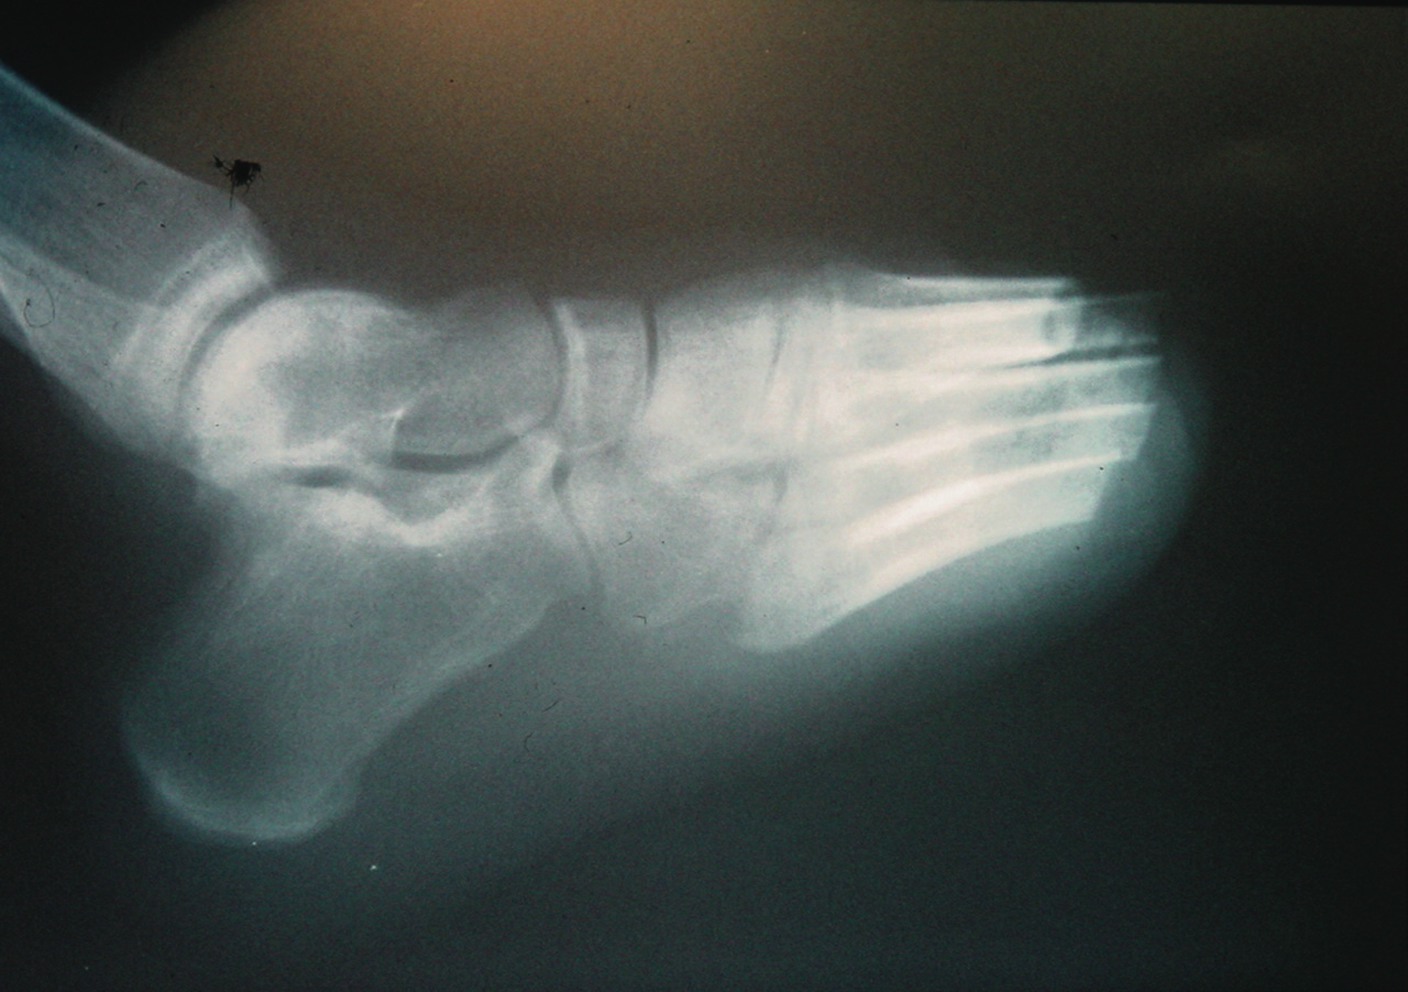

Key Insights On Performing Transmetatarsal Amputations

The surgeon must not dismiss important principles of surgery such as gentle tissue handling, hemostasis and meticulous anatomical dissection. Viable plantar soft tissues and adequate resection of osseous structures for closure are paramount. Due to decreased vascularity, one should not use a tourniquet. Tourniquets prevent the proper assessment of bleeding and damage distal bypass sites.6,28 An ankle block should be sufficient for anesthesia.28 Small towel clamps at preaxial and postaxial phalanges assist in the control of the forefoot during the dissection. The surgeon should make a full thickness dorsal incision proximal to the metatarsophalangeal joints and necrotic tissue, and continue plantarly in order to ensure an adequate plantar flap. A larger medial flap side accommodates the increased medial forefoot diameter. One should proceed to dissect the dorsal soft tissue plane from the metatarsals and follow this with disarticulation of the metatarsophalangeal joints. The transverse sectioning and beveling of the metatarsals proximal to the surgical neck in the functional metatarsal parabola optimizes the weightbearing surfaces.6 Bevel the metatarsals plantarly, with the first and fifth beveled at the medial and lateral aspects respectively.6 Within the parabola, the second metatarsal is the longest, followed by the first, the third, fourth and fifth. An oblique metatarsal break and graded step down pattern allow propulsion and preserve the gait pattern. The lack of existing osseous prominences prevents high-risk pressure areas. Remodeling the osseous resection may be necessary to remove necrotic tissues. In addition, more osseous resection increases the availability of soft tissue coverage. Prior to closure, one should reevaluate the excision of superfluous soft tissue and osseous structures. Sesamoid bones, plantar plates, nerves and tendons serve as a nidus for infection. With distal retraction of extensor and flexor tendons, one can resect tendons proximally to allow retraction.6 Resecting nerves proximally helps avoid a neuroma or neuritis on any osseous prominences.6 Employing a system that provides pulsatile irrigation and debridement can facilitate copious lavage of the surgical wound. Electrocautery prevents excessive bleeding and the formation of a hematoma.